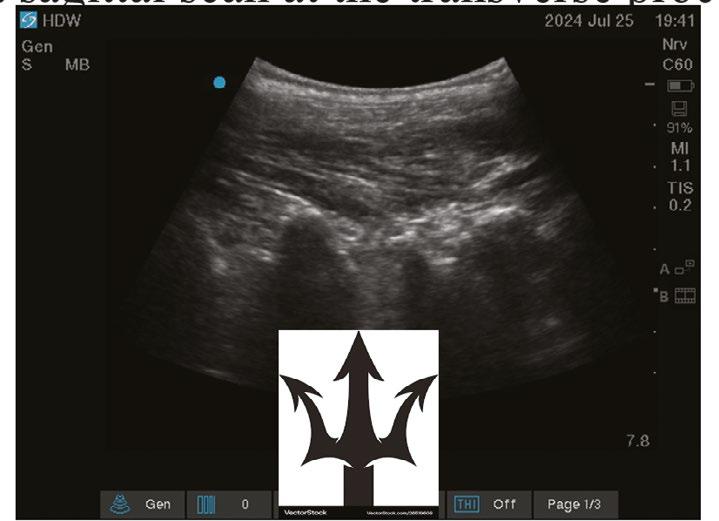

Another focus for AI in anaesthesia lies in real-time analysis of ultrasound scanning.[8] Multiple algorithms have been developed to segment and apply colour to greyscale ultrasound live images. Despite promising progress, the evidence base gathered to assess and appraise the utility of these various tools remains insufficient. Studies are too heterogenous, use differing performance metrics and ground truth definitions, or are simply not made public due to commercial sensitivity.[9]